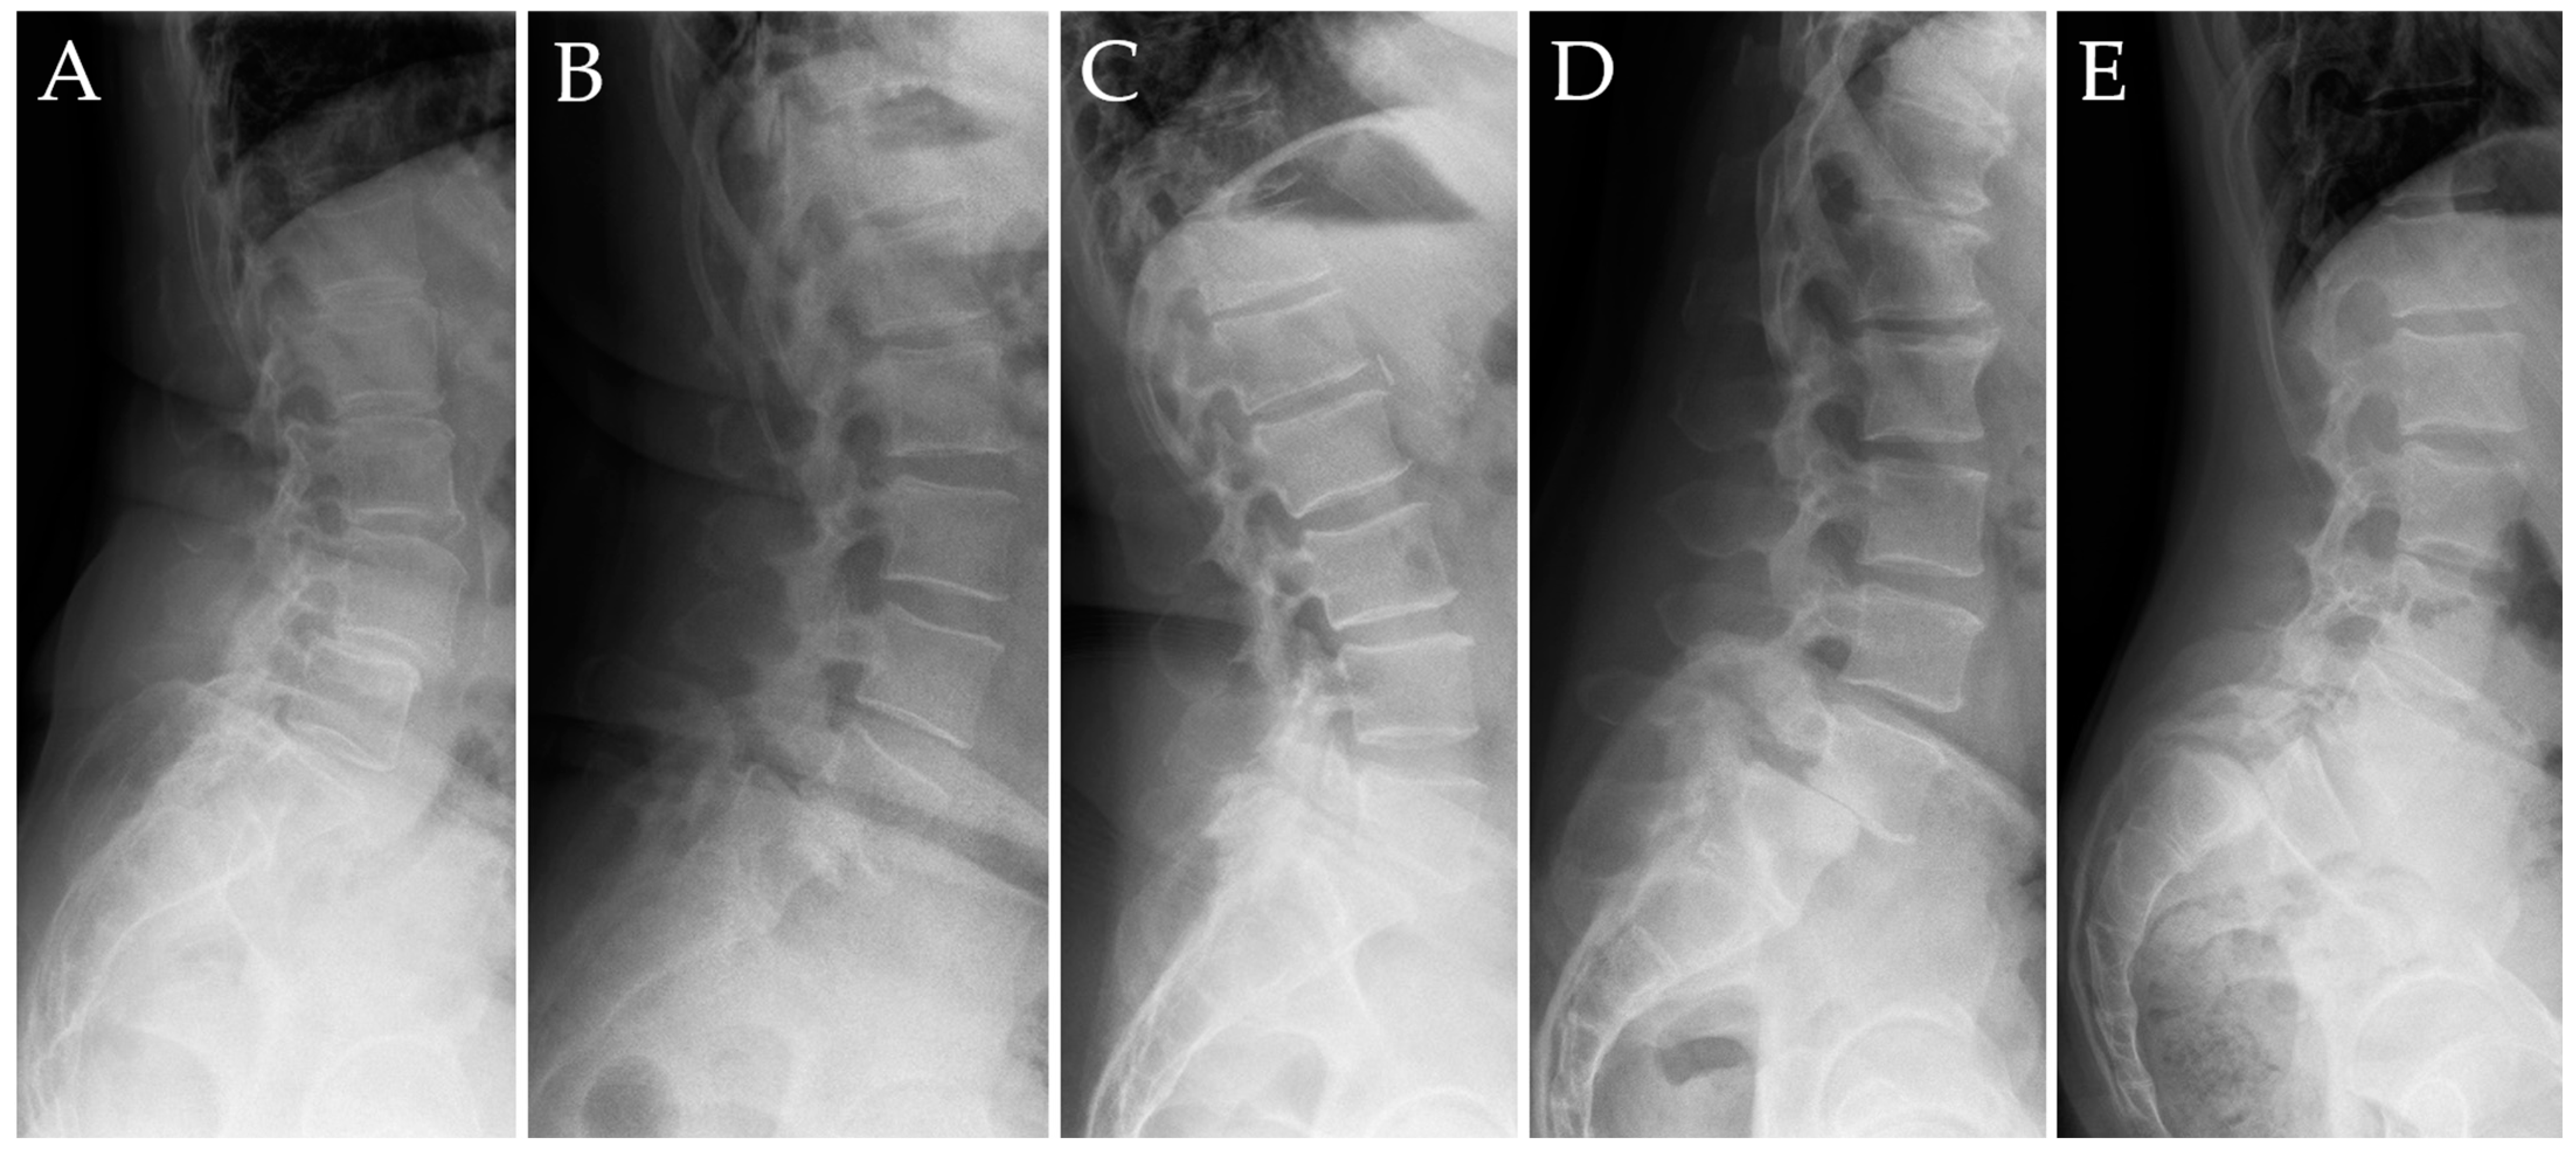

We used the Meyerding classification of the degree of vertebral slippage to analyze the preoperative spondylolisthesis grade and the postoperative result, with referral to the achieved correction in grade and millimeters [16] (Figure 2).

Figure 2. Meyerding’s classification was exemplified in 5 patients from our cohorts. (A) grade I: 0–25% slippage. (B) grade II: 25–50% slippage. (C) grade III: 50–75% slippage. (D) grade IV: 75–100%. (E) grade V: greater than 100% slippage [16].